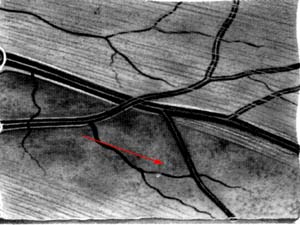

Oftalmo-neurologická diagnostika 1956, Michelem popsaný obraz si můžeme kdykoliv vyvolat, vyšetřujeme-li oční pozadí podle Vogtova návrhu bezčerveným světlem.

The temporal raphe of the human retina Amer.J.ophthal. 62:926/1966, popsal předěl ve vrstvě nervových vláken temporálně od makuly mezi horní a dolní polovinou sítnice.